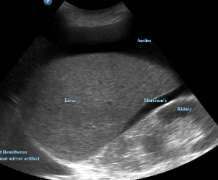

budd-chiari syndrome

TIPS

PV thrombosis